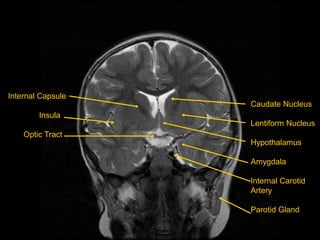

Coronal T2 Images

Internal Capsule

Insula

Optic Tract

Caudate Nucleus

Lentiform Nucleus

Hypothalamus

Amygdala

Internal Carotid

Artery

Parotid Gland